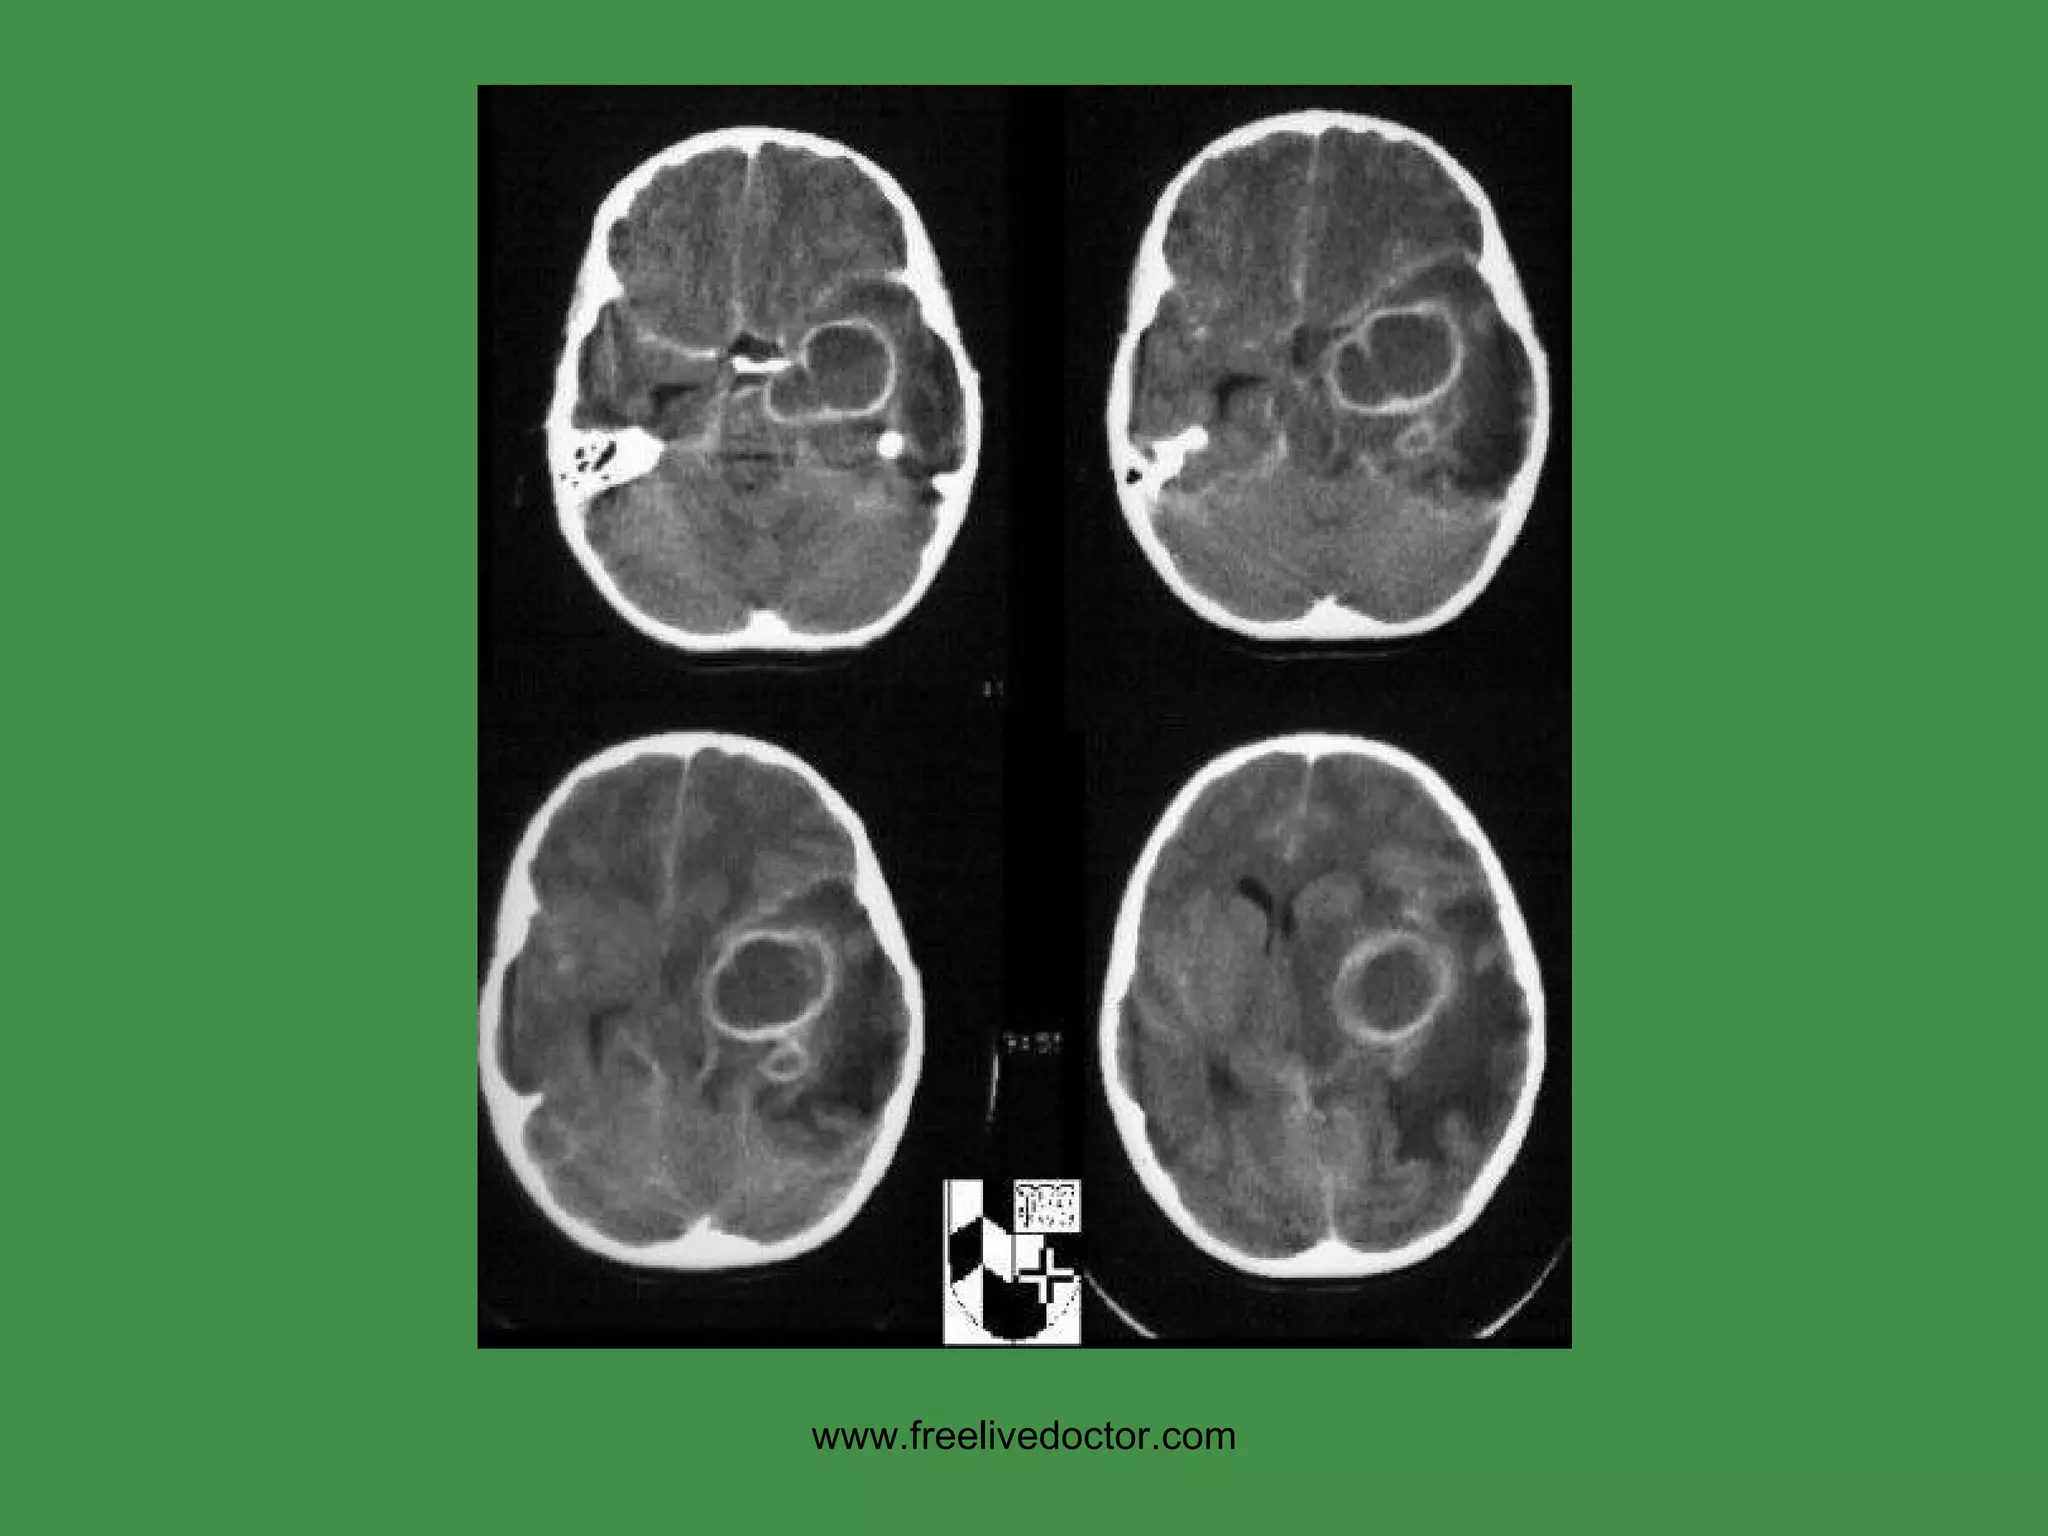

METASTATIC CNS TUMORS LUNG BREAST MELANOMA KIDNEY GI www.freelivedoctor.com

“ PARA”NEOPLASTIC SYNDROMES SMALL CELL, LUNG LYMPHOMAS BREAST CA Purkinje Cell Degeneration Encephalitis, Limbic System Sensory Neuron Degeneration, DRG Eye Movement Disorders www.freelivedoctor.com

• #165 Toxoplasmosis and lymphomas and encephalitis are very common in AIDS. Might you cal the MRI lesion a “toxoplasmoma”? Ans: Sure

• #166 A solitary brain mass is statistically just as likely to be metastatic than primary